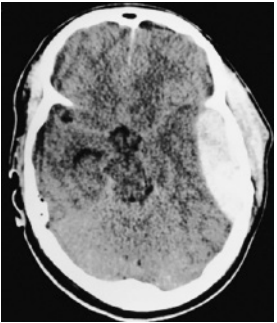

Paciente do sexo masculino, 23 anos, foi vítima de acidente automobilístico no qual o veículo em que estava colidiu com caminhão. Usava cinto de segurança e foi retirado consciente do carro pela equipe de resgate. Apresentava amnésia anterógrada. Após atendimento pré-hospitalar, o paciente foi levado ao pronto-socorro, sem déficits motores ou sensitivos. No hospital, o médico pede uma tomografia computadorizada de crânio para avaliação. Alguns minutos depois, a equipe de enfermagem solicita avaliação de emergência para o paciente, com necessidade de intubação orotraqueal por rebaixamento do nível de consciência e anisocoria com pupila esquerda dilatada. Tomografia computadorizada de crânio sem contraste

Enunciado 4428012-1

Ao considerar a situação clínica do paciente e a imagem tomográfica apresentada, o médico diagnosticou